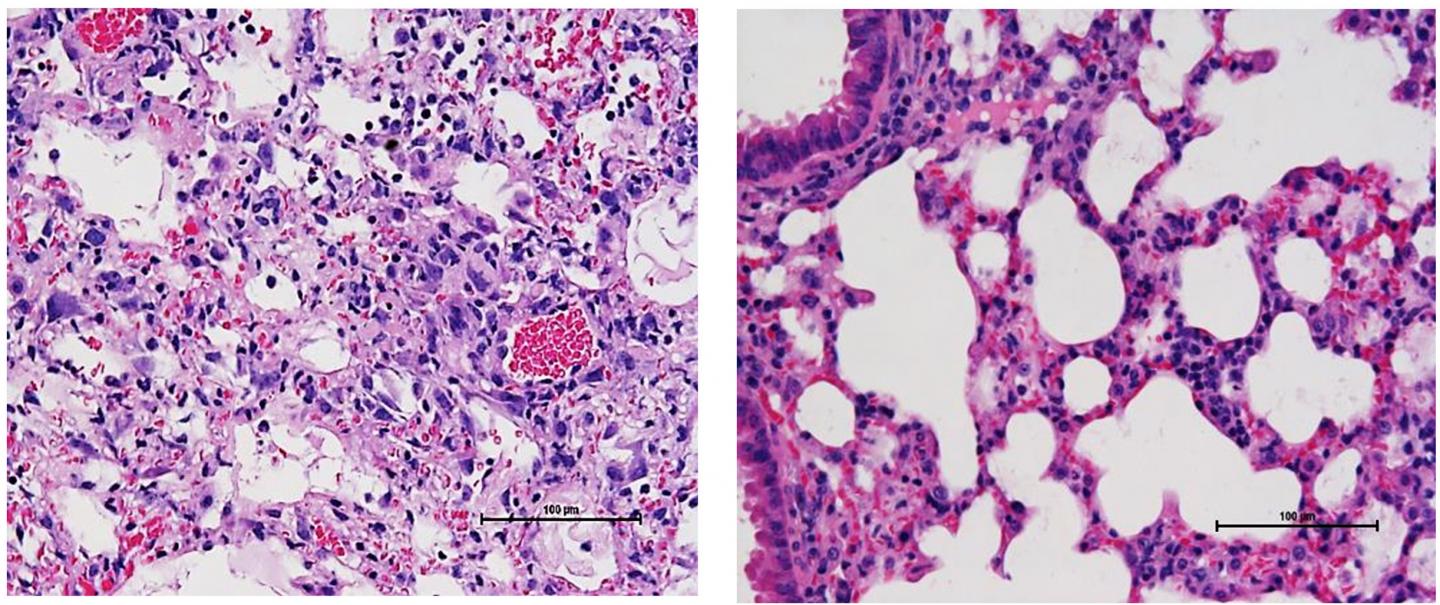

Sun and colleagues now reveal that this may be because the patients' white blood cells cause extensive damage to their lungs. Though the macrophages and neutrophils of mice co-infected with influenza and MRSA were defective at killing bacteria, reactive oxygen species released by these cells induced the death of inflammatory cells within the lungs, lethally damaging the surrounding tissue. Inhibiting NADPH oxidase 2 (Nox2), the enzyme that produces reactive oxygen species in macrophages and neutrophils, reduced the extent of this damage and, when combined with antibiotic treatment, boosted the survival of co-infected mice.